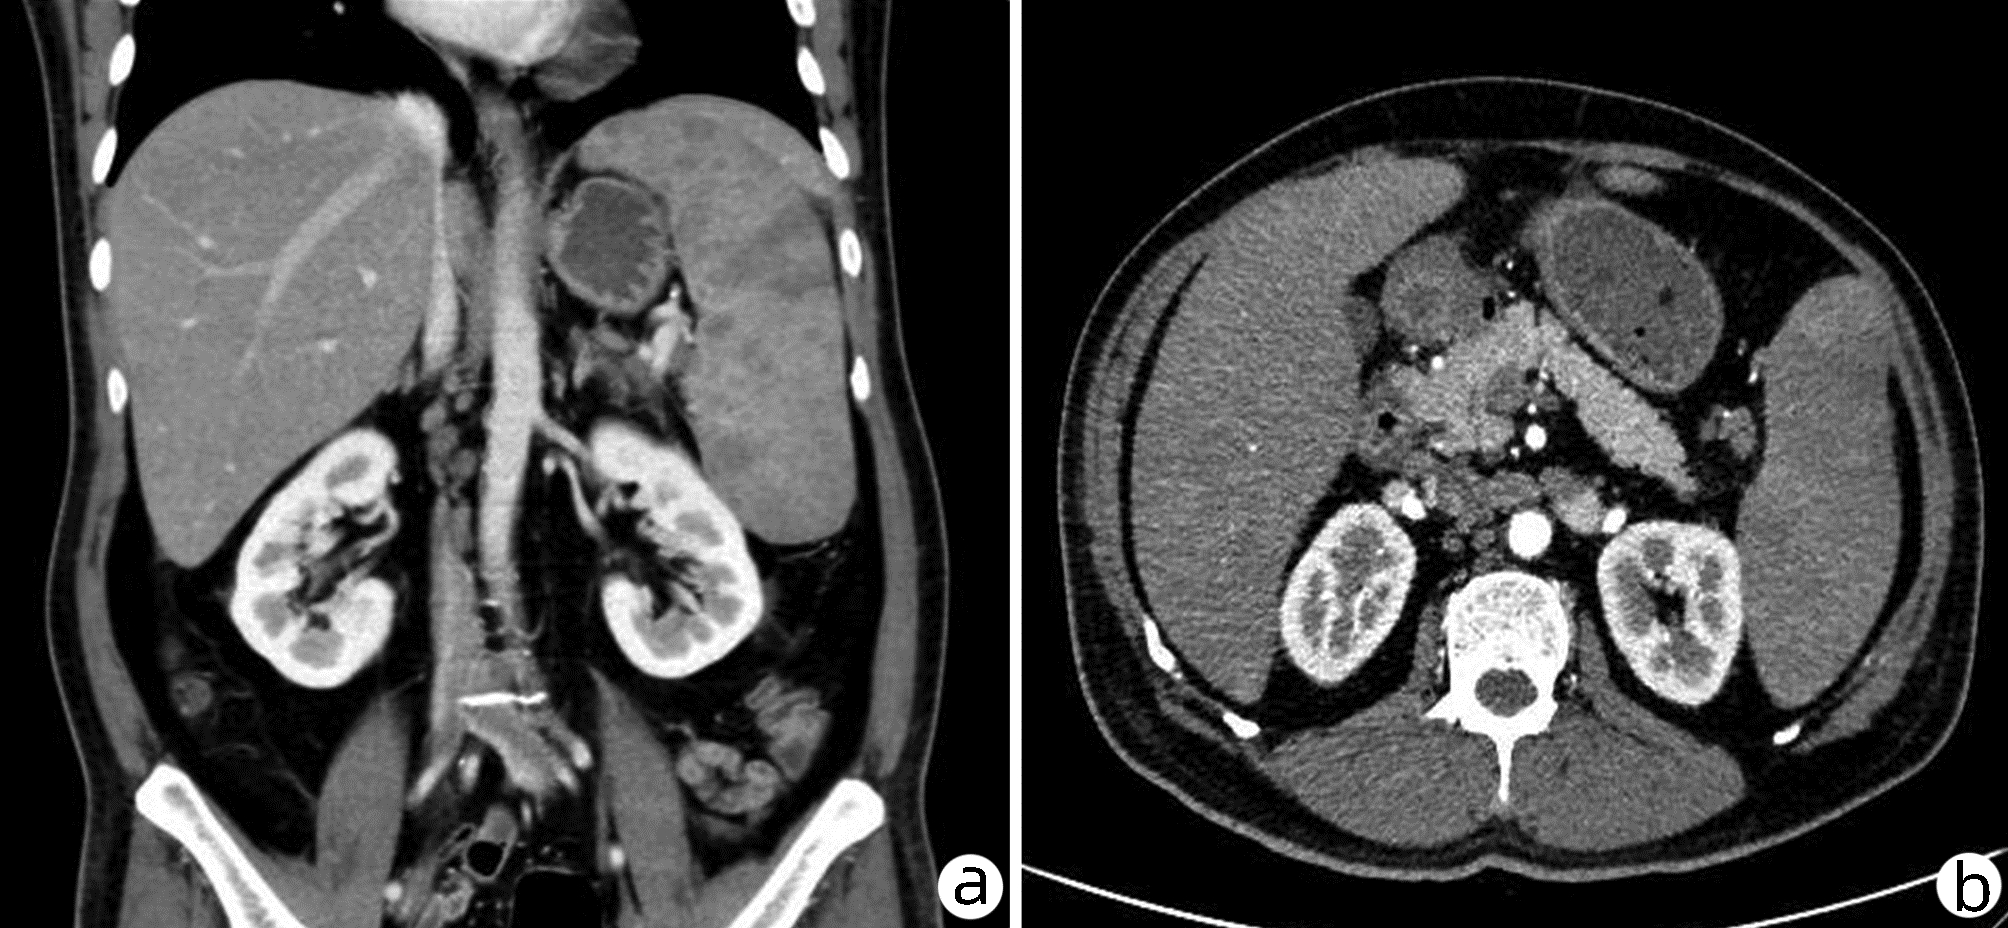

Diffuse large B-cell lymphoma with severe cholestasis as the main manifestation: A case report

Huaqian XU, Meng WEI, Xue ZHANG, Hai YI, Fangyi FAN, Aiping HUANG, Shanhong TANG

2022, 38(12): 2821-2823. DOI: 10.3969/j.issn.1001-5256.2022.12.025

Abstract(2140) HTML (1052) PDF (2629KB)(96)

Abstract: